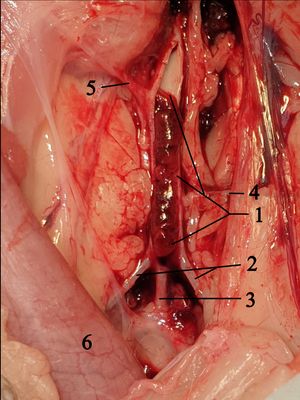

외과적 중격 절제술은 내과적 치료에 반응하지 않는 심한 증상을 가진 환자에게 시행되는 개심술이다. 1960년대 초부터 성공적으로 시행되어 왔다.[19] 외과적 중격 절제술은 좌심실 유출로 폐색을 일관되게 감소시키고 증상을 개선하며, 경험이 풍부한 의료기관에서는 수술 사망률이 1% 미만이며 85%의 성공률을 보인다.[39]이 수술은 정중 흉골 절개술(전신 마취, 흉부 개방 및 체외 순환)과 심실 중격의 일부를 제거하는 것을 포함한다.[38] 벤투리 효과를 줄이기 위해 유출로의 크기를 늘리는 데 초점을 맞춘 외과적 절제술은 승모판의 전방 잎의 수축기 전방 운동(SAM)을 없애기에 부적절할 수 있다. 이렇게 제한적인 절제술을 시행하면 잔여 중격 돌출부가 여전히 혈류를 후방으로 되돌려 SAM이 지속되기 때문이다. 중격 돌출부의 더 깊은 부분을 절제해야만 혈류가 승모판에서 멀리 떨어진 전방으로 되돌려져 SAM이 사라진다.

이를 염두에 두고 모로우 절제술을 변형한 확장 절제술, 유두근의 동원 및 부분 절제술이 최선의 절제술이 되었다.[54][55][56][57] 특히 크고 과도한 승모판을 가진 환자의 경우, 승모판과 유출로의 완전한 분리를 위해 전방 잎 주름 성형술을 추가할 수 있다.[57] 중격 절제술의 합병증으로는 사망 가능성, 부정맥, 감염, 지속적인 출혈, 중격 천공/결손 및 뇌졸중 등이 있다.[39]

- 외과적 중격 절제술: 내과적 치료에 반응하지 않는 심한 증상을 가진 환자에게 시행되는 개심술이다. 1960년대 초부터 시행되었으며,[19] 좌심실 유출로 폐색을 감소시키고 증상을 개선한다. 숙련된 의료기관에서는 수술 사망률이 1% 미만, 성공률은 85%이다.[39] 합병증으로는 사망, 부정맥, 감염, 출혈, 중격 천공/결손, 뇌졸중 등이 있다.[39]